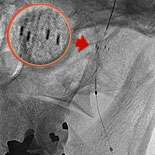

Fig 2: A carotid filter balloon, an umbrella like device, is shown after insertion into the left carotid artery in Ralph's neck.

The cutting edge treatment is to insert a carotid filter balloon which is an umbrella like device used to catch debris as the artery is being opened. Fig.1 shows Ralph's narrowing of the left carotid artery. Fig.2 shows the device being inserted in Ralph's artery. In fig.3 the carotid balloon's up showing inflation of the balloon which opens the blocked artery. A stent (fig.4) which is a metallic cage is placed in the artery to keep it opened.